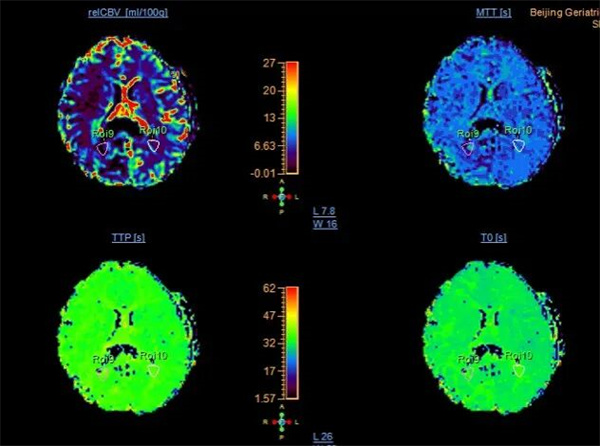

▲右侧顶枕交接区病变灌注较对侧(正常)部位增加,表现为rCBF和rCBV增加。

影像结果提示“右侧顶枕交界区考虑肿瘤复发可能”,为临床后续精准制定治疗方案提供了关键依据。检查结束后,张平主任第一时间用通俗语言向家属解读结果,耐心解答疑问;护士与技师则同步开展术后宣教,详细叮嘱饮食、休息及复查注意事项。家属对科室专业的技术水平与贴心的服务态度高度认可,出院前多次向医护团队表达感谢。